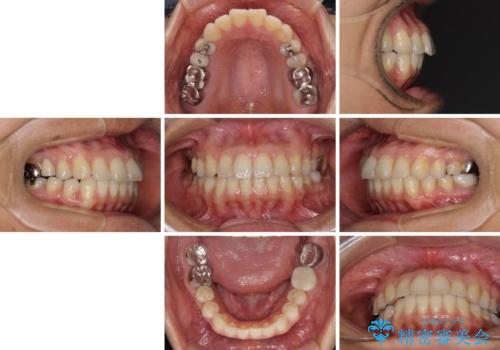

- 高校生の時に行った矯正治療の後戻りと、通院してもなかなか改善しない奥歯の痛みを気にして来院された患者様です。

左下奥歯は、前医より難治性なので抜歯も考えるよう言われたそうですが、一度もラバーダムを用いた根管治療はされていないとのことでした。

まずは左下奥歯の根管治療を行い、痛みが引いたことを確認してから矯正治療を開始しました。

後戻りは軽微であったため、インビザライン・ライトにて歯列を整えました。

根管治療を行う上で、ラバーダム防湿は処置の中で最も重要な要素です。